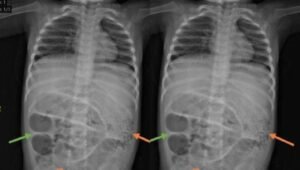

Gejala Aneh: Perut Membesar dan Sulit Buang Air Besar Seorang anak kecil dilarikan ke rumah…

Usus Penuh Cacing